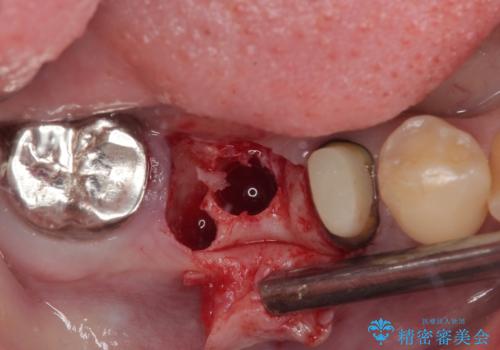

左下小臼歯は根管治療で対応する予定でしたが、診断のために歯肉を開いたところ頬側に垂直破折が認められたため、抜歯即時埋入インプラントによる補綴治療を選択することとしました。

右下は大臼歯部の歯は抜歯即時埋入インプラントにて、手前の歯は保存して補綴治療を行うこととしました。